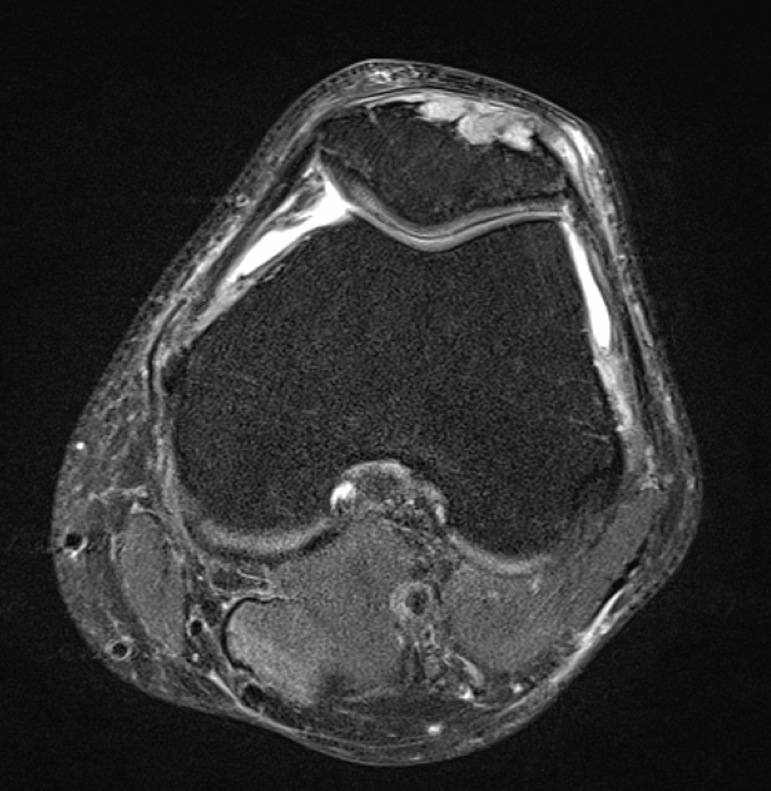

Figure 4 for case gout arthritis ( RID3567 )

Figure 4